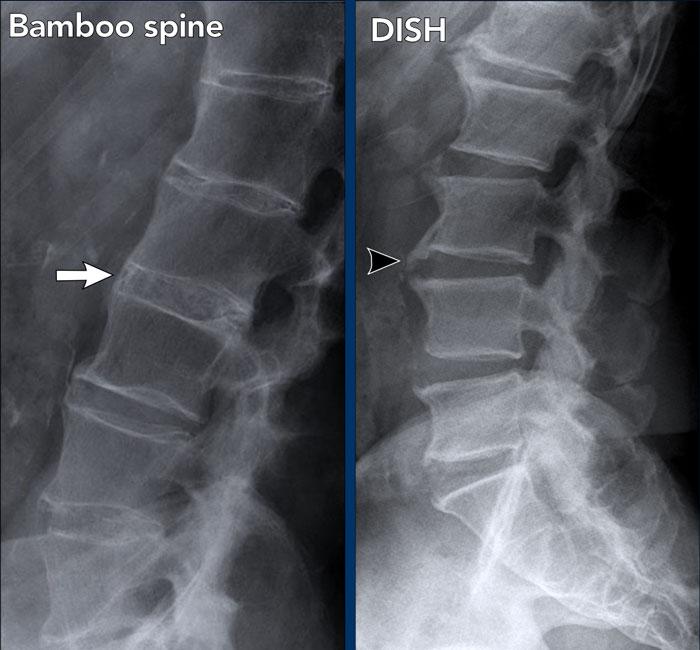

DISH không nên nhầm lẫn với hình ảnh cột sống tre, vốn là dấu hiệu đặc trưng của viêm cột sống dính khớp.

Hình ảnh

- Cột sống tre: hợp nhất cột sống thắt lưng do các gai xương syndesmophyte nhỏ và cốt hóa dây chằng cạnh cột sống.

- DISH: cốt hóa và vôi hóa cồng kềnh của dây chằng dọc trước và mô liên kết cạnh cột sống trên hơn 4 tầng đốt sống liên tiếp. Điển hình là chiều cao đĩa đệm được bảo tồn, không có thoái hóa đĩa đệm nặng nề.

Các nguyên nhân khác gây cốt hóa dây chằng cột sống bao gồm thoái hóa khớp nặng, và ít gặp hơn là ngộ độc vitamin A và bệnh fluorosis.